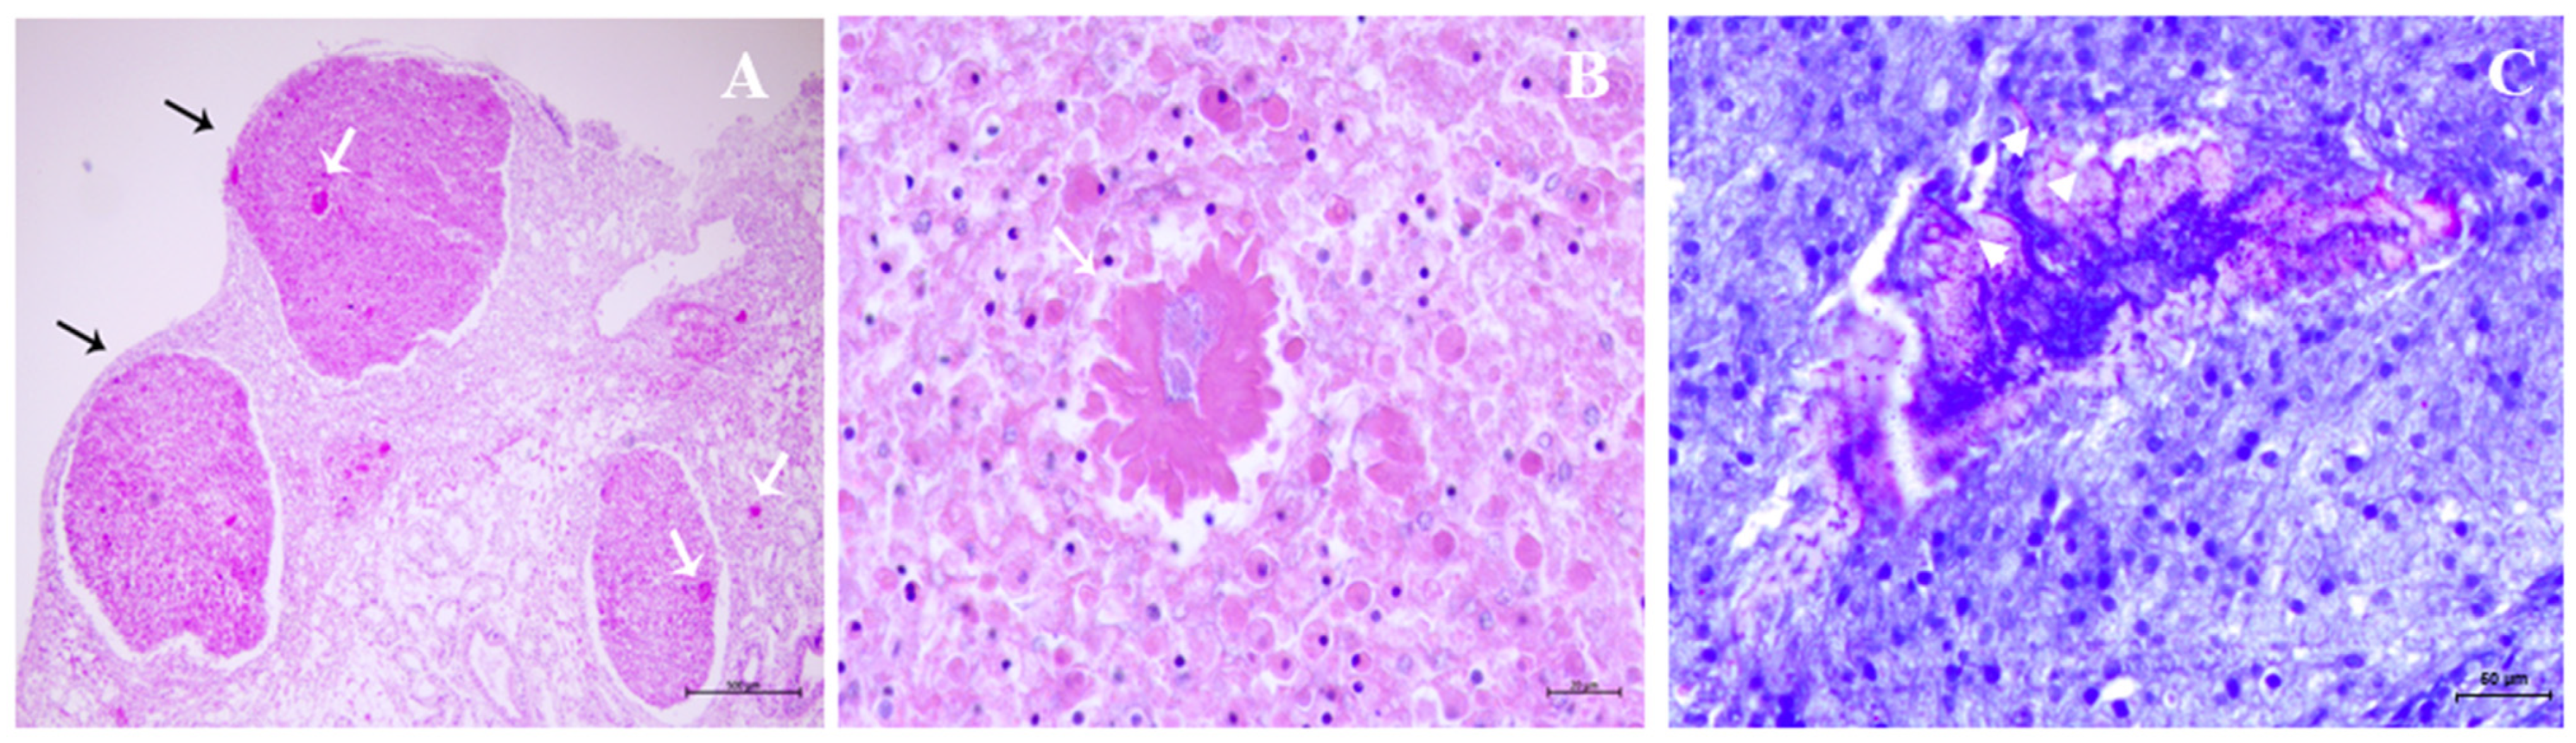

2.6. Gross and Microscopic Findings